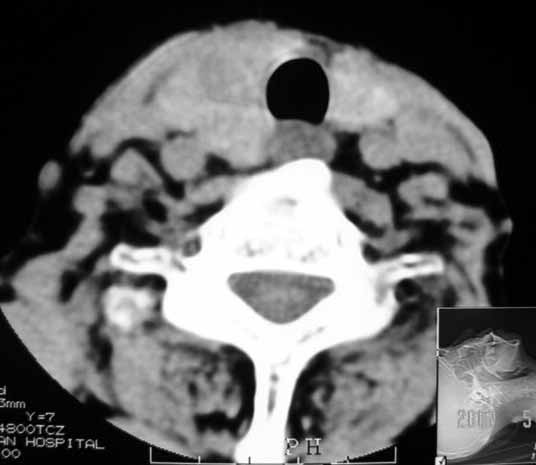

以下是引用jw-830在2007-5-24 15:33:00的发言:[br]右侧甲状腺增大,内可见低密度,病灶与周围软组织界线欠清晰,建议增强扫描除外甲状腺癌

以下是引用adams在2007-5-24 17:15:00的发言:[br]支持“ 右侧甲状腺增大,内可见低密度,病灶与周围软组织界线欠清晰,建议增强扫描除外甲状腺癌”。 [br] [br] [br][br] [br] [br]

以下是引用苯小孩在2007-5-24 15:26:00的发言:[br]左侧甲状腺腺癌或瘤,建议穿刺或核素进一步检查.